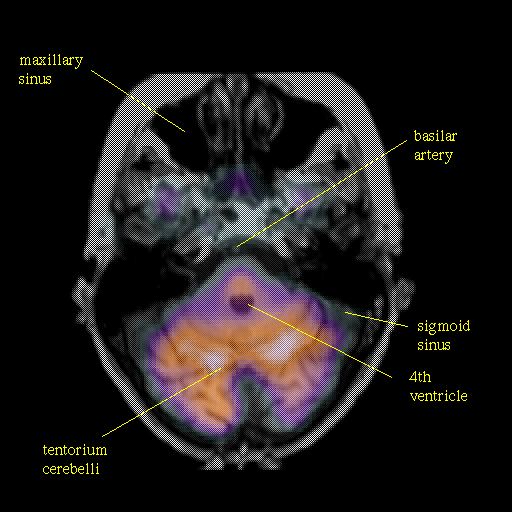

overlay: Slice 14

Slice 14

Pointers

Labeled